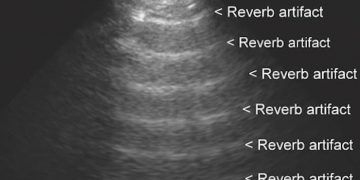

Etiket: Yineleme Artefaktı Anlamı